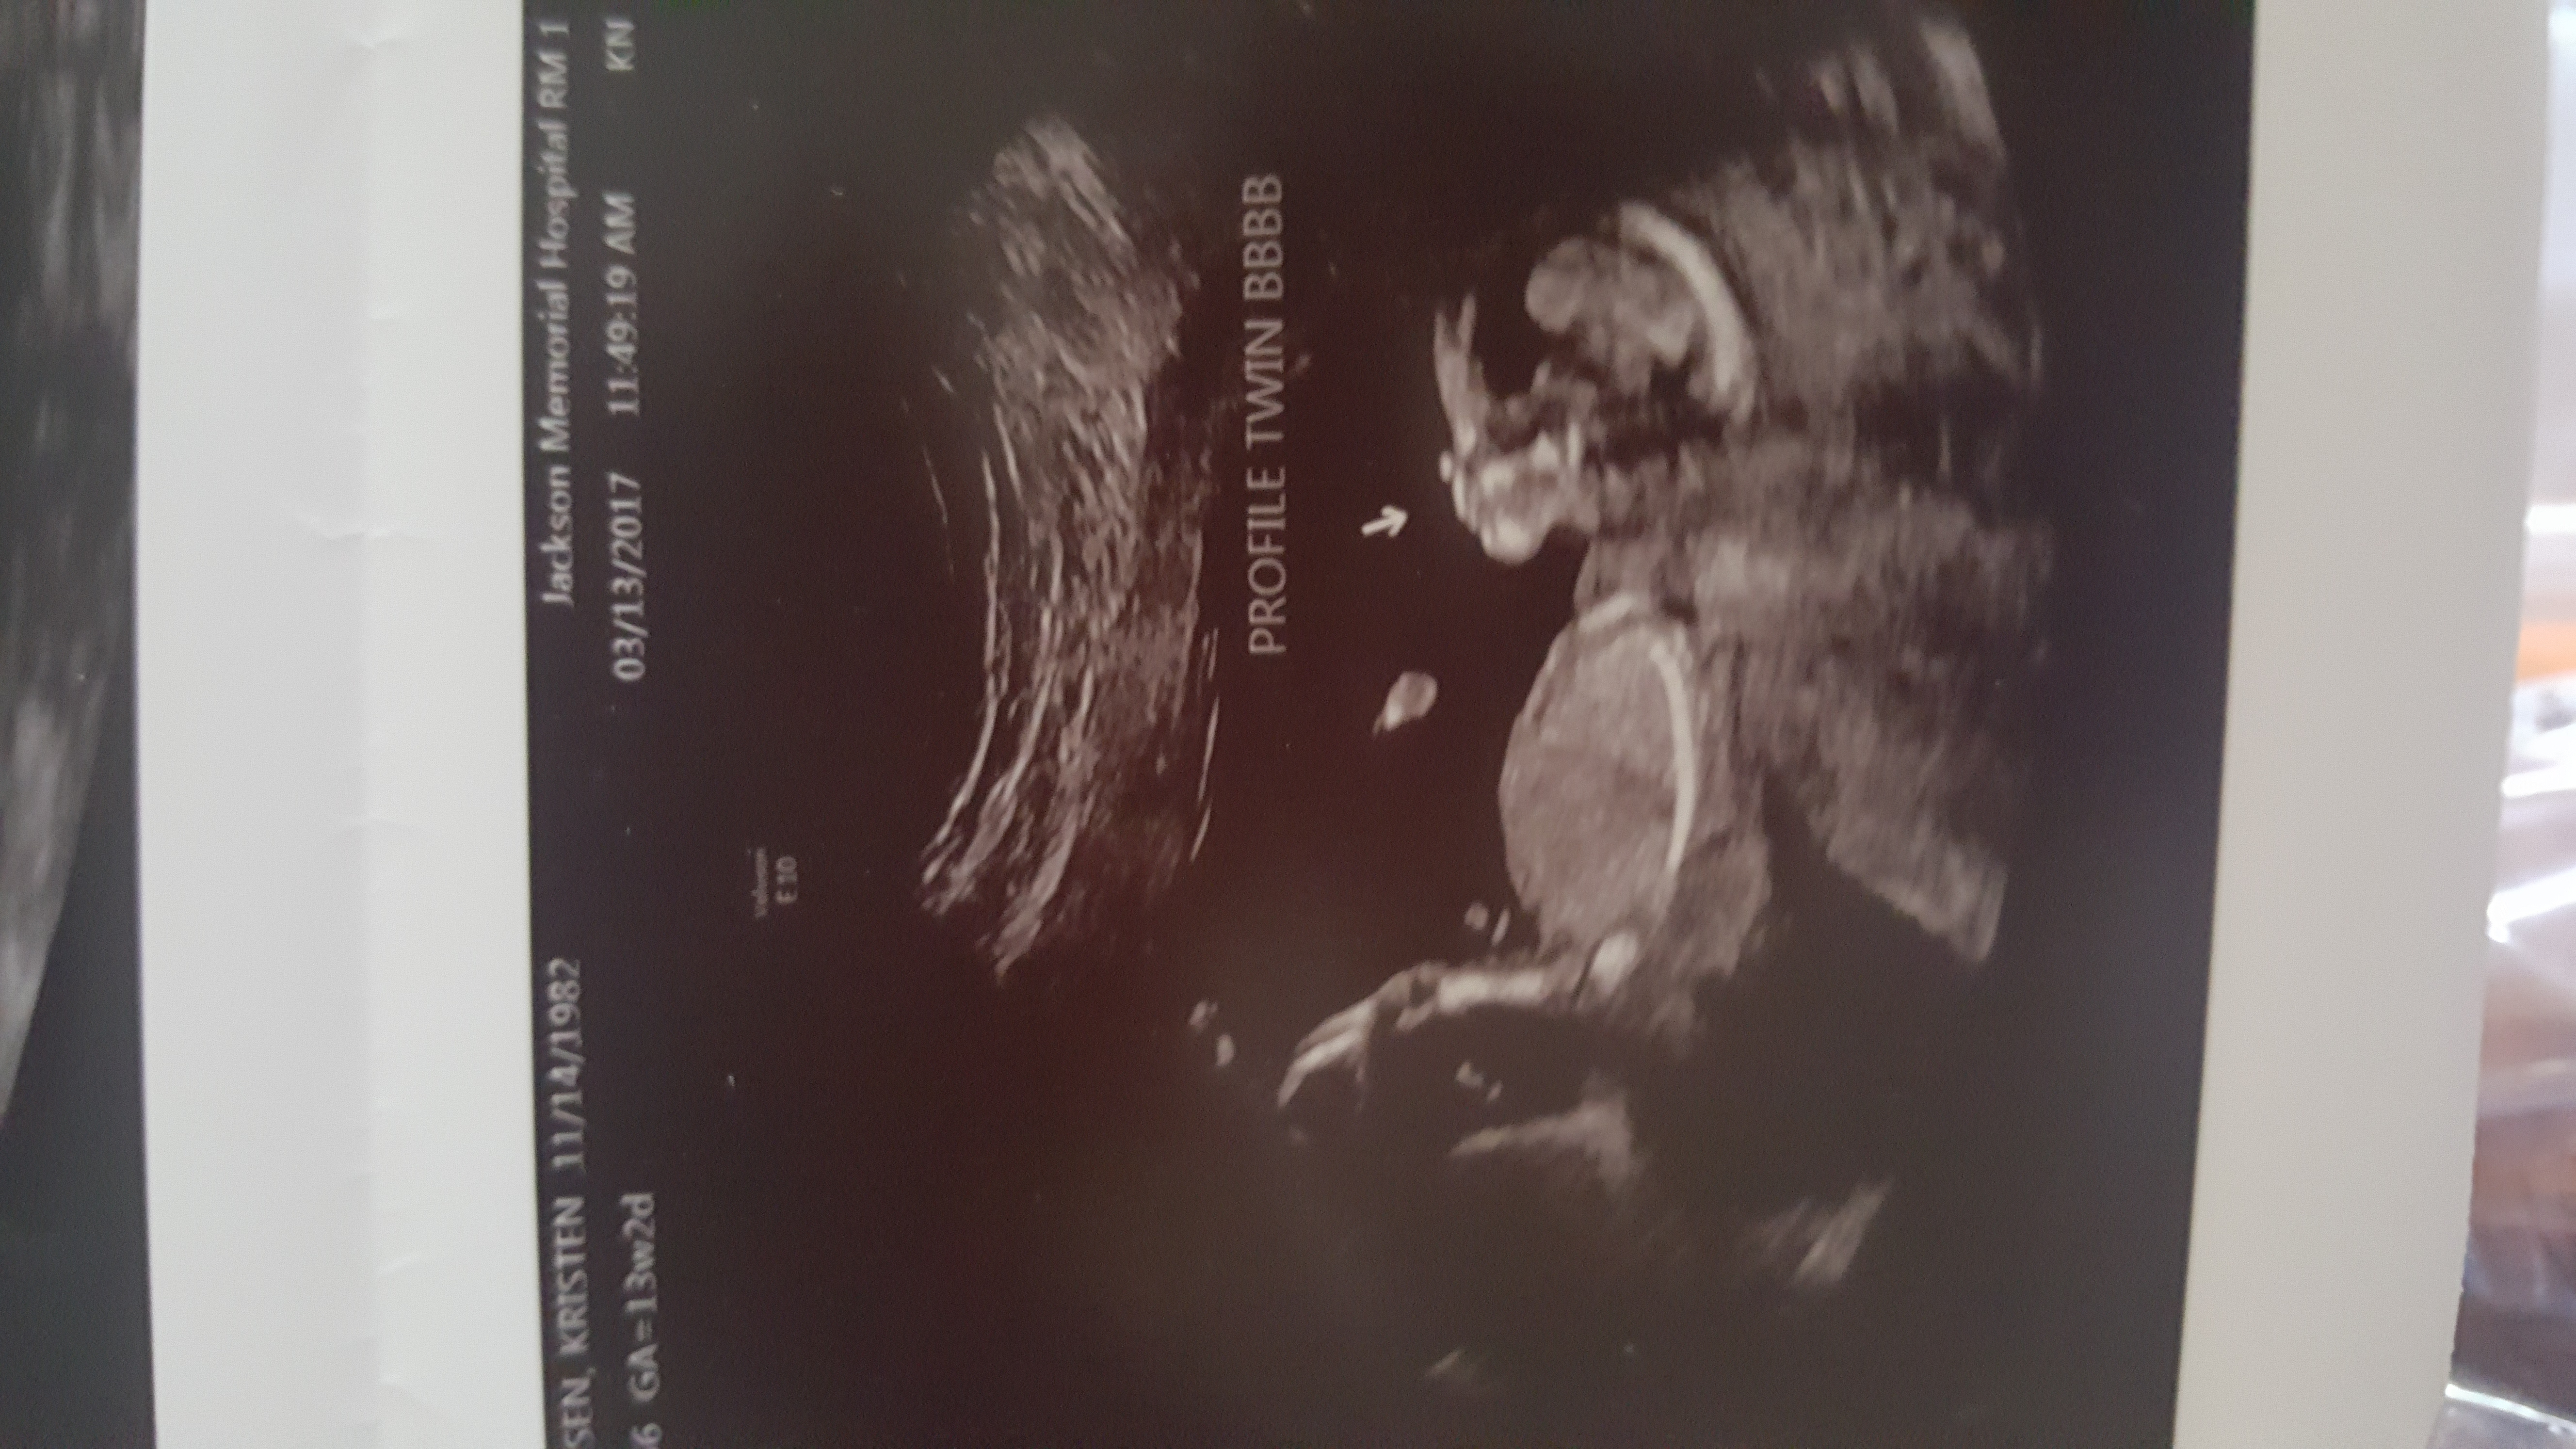

Gender guess 13w2days

Hi, i am new to here; I've been stalking and reading threads for a few months but never posted. I did some reading on the nub theory and have looked at countless scans, even taken some of those quizzes, but i can't tell on mine. Don't even know if it's a good enough shot to tell really. How do you know where the spine is??

This is our third and we already have two boys, so I'm really hoping for girl but it looks like a boy to me from this. This was a confirmed twin pregnancy but baby A died at 8wks, i found out at 11 wks both that it was twins and only one. We were looking at everything the tech was scanning just to be sure this one was ok that i never really looked for the nub like i had originally planned to do.

The leg is in the way of the nub. Share all pic you have, just in case there is one with a nub. Do you have a video perhaps?